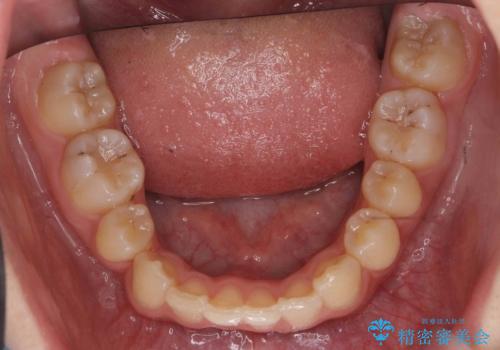

埋まっている犬歯を抜歯して、歯列矯正

- 右上の犬歯が埋伏していたため、抜歯しました。

その後、右下の小臼歯を1本抜歯し、ワイヤー矯正を行いました。

犬歯の代わりに小臼歯を配列し、最小限の抜歯の本数としました。

犬歯の両側の歯に関しては移動することにより歯槽骨が順調に回復し、上顎洞底の形態にかかわらず歯根のパラレリングを行うことができました。